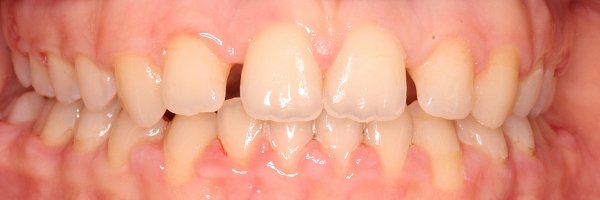

Пациентка 8 лет. Обратились с жалобой на неровное прорезывание зубов и дефицит места для постоянных зубов.

План лечения:

1)использование несъемного аппарата для расширения верхней челюсти Марко Росса

2)Через 4 месяца установка частичной брекет-системы 2 на 4 для выравнивания передней группы зубов;

Срок лечения составил 10 месяцев.

Достигнуты результаты:

— изменение ширины верхнего зубного ряда, что способствует нормальному прорезыванию постоянных зубов;

— устранена эстетическая недостаточность, связанная со скученностью зубов верхней челюсти.